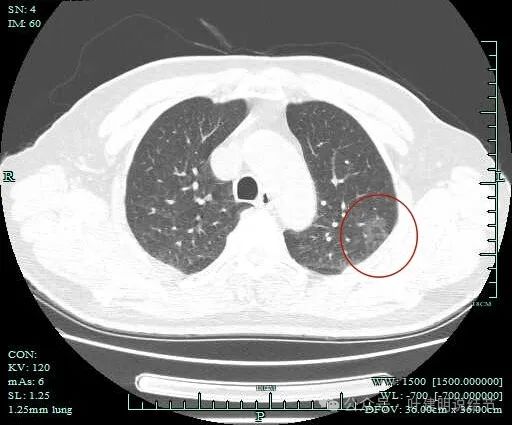

灶内密度感觉欠均匀,虽然无明显实性成分。

灶内似有血管穿行与小空泡征,表面有细毛刺。